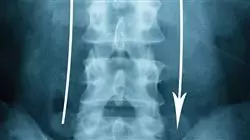

1.1.1. Imágenes en las fracturas toraco-lumbares y sacro

1.1.1.3. Manejo y uso de las imágenes radiológicas

1.1.1.4. Definir las indicaciones del Uso apropiado del TAC o RMN

1.1.2.2. Diferenciar entre las clasificaciones de Denis, AO y TLICS